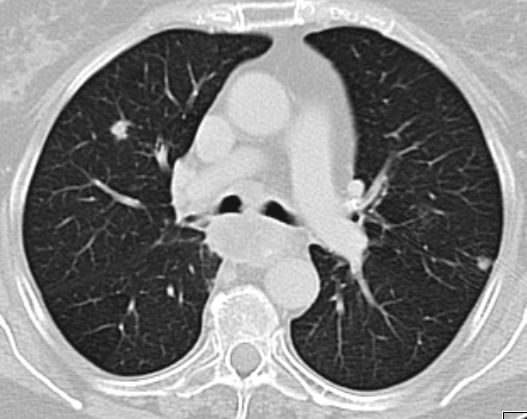

| Lunge | 58-jährige Frau, die vor 3,5 Jahren ein

Endometriumkarzinom pT2 pNo(0/33) Mo G1 hatte. 10 Monate später Pleuraerguss,

pulmonale Metastasen. Jetzt 3. Progress Carboplatin, Taxol, MPA.![]() |